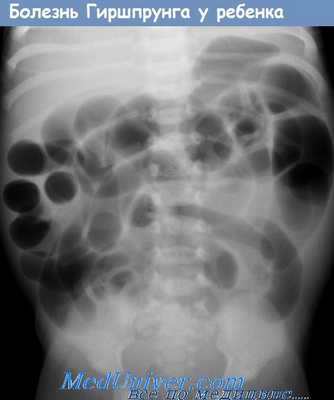

- Рентгенограмма брюшной полости. Для дуоденальной обструкции патогномоничен симптом "bubble double" — наличие двух газовых пузырей в области желудка и 12-перстной кишки. Врожденная низкая непроходимость проявляется множественными горизонтальными уровнями жидкости, которые соответствуют перерастянутым отделам тонкой и толстой кишки.

- Рентгенография брюшной полости. Патогномоничный симптом кишечной непроходимости — чаши Клойбера, которые представляют собой перерастянутые петли кишки, заполненные калом и газами. На рентгенограмме заметен симптом перистости (отечные складки слизистой).

Толстокишечная непроходимость

На 2—3-й день жизни возникает непереносимость пищи, рвота с примесью желчи и вздутие живота. Живот при пальпации мягкий, тестоватый. На обзорной рентгенограмме брюшной полости видны многочисленные расширенные кишечные петли без уровней жидкости (низкая кишечная непроходимость), иногда нижний правый квадрант живота имеет вид матового стекла (симптом Нейхаузера). Ирригоскопия выявляет микрокодов и многочисленные мелкие дефекты наполнения в терминальной части подвздошной кишки (густой меконий). В противоположность большинству форм кишечной непроходимости у новорожденных, при мекониальном илеусе к хирургическому вмешательству прибегают только при неэффективности консервативного лечения, сочетанию с другими пороками развития (например, атрезией кишки) или осложнениях (завороте или перфорации кишки).

Обычно болезнь Гиршпрунга наблюдается как изолированный порок развития, по у 10% больных имеется трисомия 21-й хромосомы. У новорожденных с болезнью Гиршпрунга наблюдается нарастающее вздутие живота, рвота, замедленное отхождение мекония или его отсутствие в первые 48 часов жизни. В более старшем возрасте характерны постоянные запоры, вздутие живота, истощение. Объективный осмотр выявляет только резкое вздутие живота. Рентгенологические данные указывают на низкую кишечную непроходимость. Ирригоскопия облегчает диагноз.